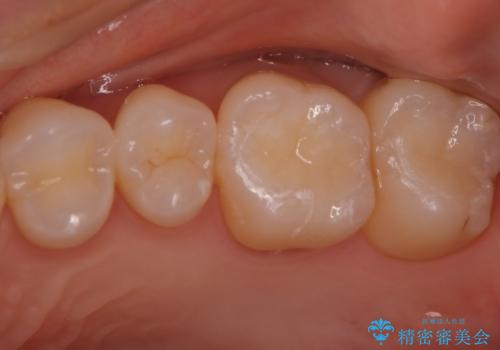

目立つ銀歯を白くしたい セラミック治療

虫歯をとり、銀歯から白いセラミックになったためかなり喜んでいただきました。